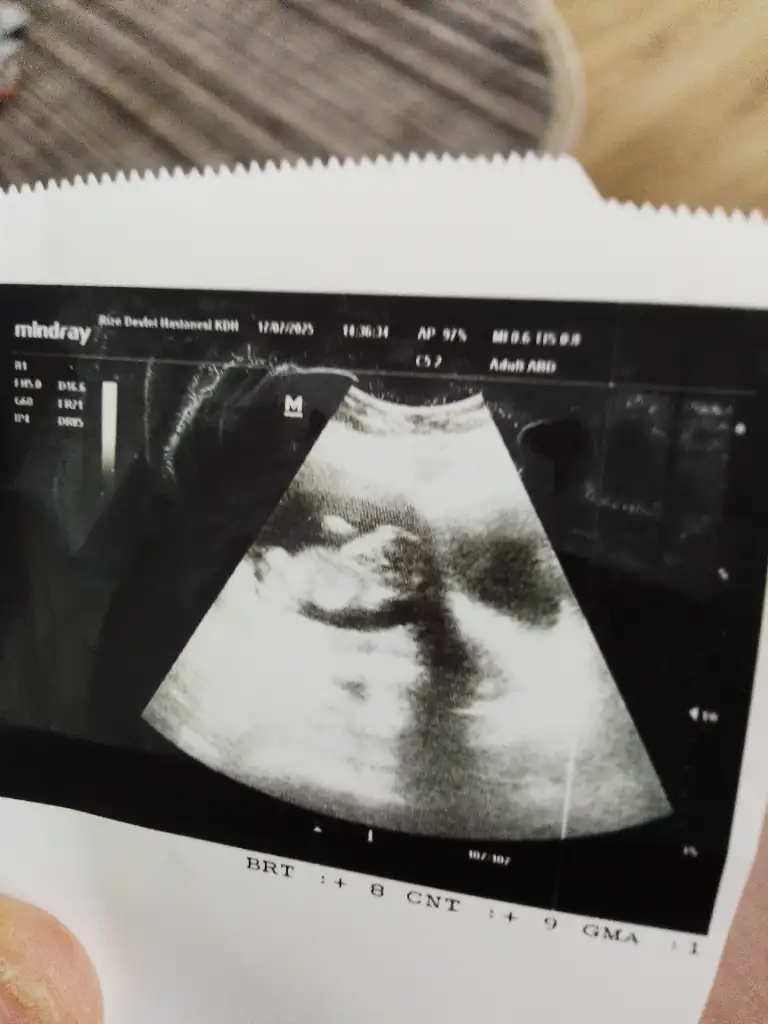

Ben herkese erkek demiyorum , gönderilen resimlerde kimi söylüyorum

Benim nedir sizce 6+4Sizinde erkek![]()

Ben keseden anlamiyorum kese teorisine de inanmiyorum zatenBenim nedir sizce 6+4

Merak işteBen keseden anlamiyorum kese teorisine de inanmiyorum zaten![]()